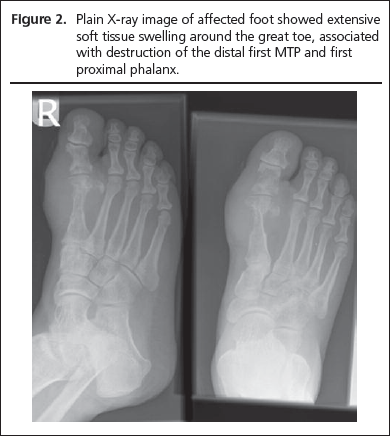

A 71 year old Asian man with type 2 diabetes and hypertension (treated with lisinopril) was referred by his general practitioner with a 4 month long history of swelling and minute superficial ulceration on the medial aspect of the right first MTP joint (Figure 1). He had received two courses of empirical antibiotic therapy prior to presentation to the foot clinic. X-ray of the right foot showed widespread destruction of the distal shaft of the first metatarsal and first MTP joint (Figure 2). Biochemical profile showed a white blood cell count of 9100/ml, C-reactive protein 163 mg/dl (NR: 0 to 10) and HbA1c of 61 mmol/l (7.7%). Swabs from the ulcer revealed Staphylococcus aureus and haemolytic streptococcus. The initial clinical suspicion was infected superficial diabetic foot ulcers with underlying osteomyelitis and the patient was treated with oral antibiotics for four weeks guided by culture and sensitivity reports. However, there was little suggestion of healing and the foot continued to remain hot and swollen with persistent ulceration. A CT scan of the affected foot showed circumferential bone erosion and soft tissue mass suggestive of tophaceous deposit around the first MTP joint (Figure 3). Serum urate level was elevated at 694 µmol/l (NR: 200-430). Joint fluid aspiration revealed negatively birefringent crystals.

Figure 1

Figure 2

Figure 3